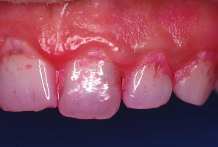

La gingivitis, es la inflamaci�n superficial de las enc�as causada por irritantes de las bacterias presentes en la boca (placa dental o bacteriana), y es com�n en todas las edades, incluyendo en escolares.